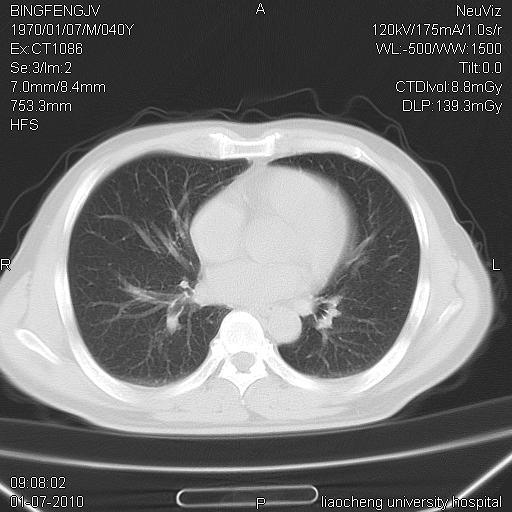

标题: CT23764B:男 40 肺部CT

治疗2周后

炎症性病灶,继发性改变。

考虑左肺上叶近胸膜下炎症并肺气囊形成。

炎症,大部吸收。